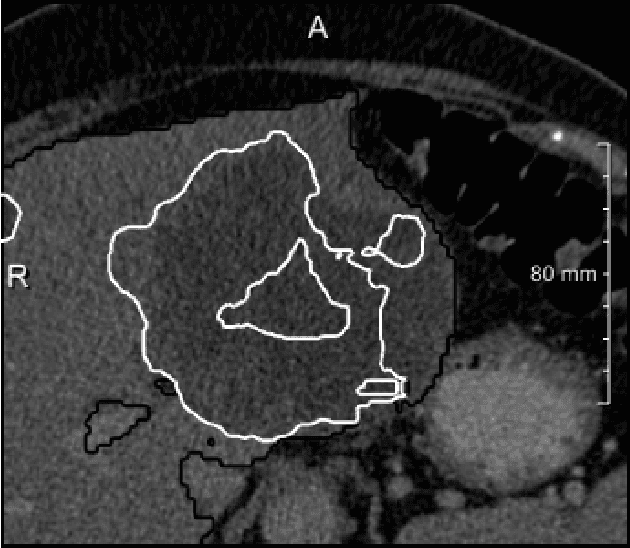

We present a fully automatic method employing convolutional neural networks based on the 2D U-net architecture and random forest classifier to solve the automatic liver lesion segmentation problem of the ISBI 2017 Liver Tumor Segmentation Challenge (LiTS). In order to constrain the ROI in which the tumors could be located, a liver segmentation is performed first. For the organ segmentation, an ensemble of convolutional networks is trained to segment a liver using a set of 179 liver CT datasets from liver surgery planning. Inside of the liver ROI a neural network, trained using 127 challenge training datasets, identifies tumor candidates, which are subsequently filtered with a random forest classifier yielding the final tumor segmentation. The evaluation on the 70 challenge test cases resulted in a mean Dice coefficient of 0.65, ranking our method in the second place.